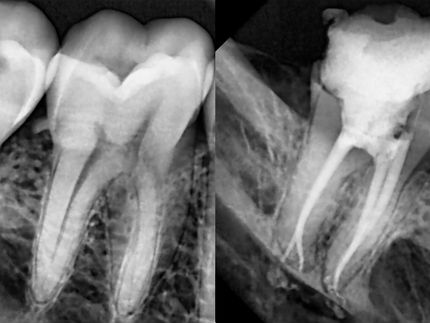

Endodontic treatment aims to repair and save a badly damaged infected tooth. the procedure involves removing the damaged pulp or nerve, cleaning disinfecting it, and then filling and sealing it.

The following cases were done using MTWO rotary endodontic instruments by VDW for fast and safe root canal preparation.